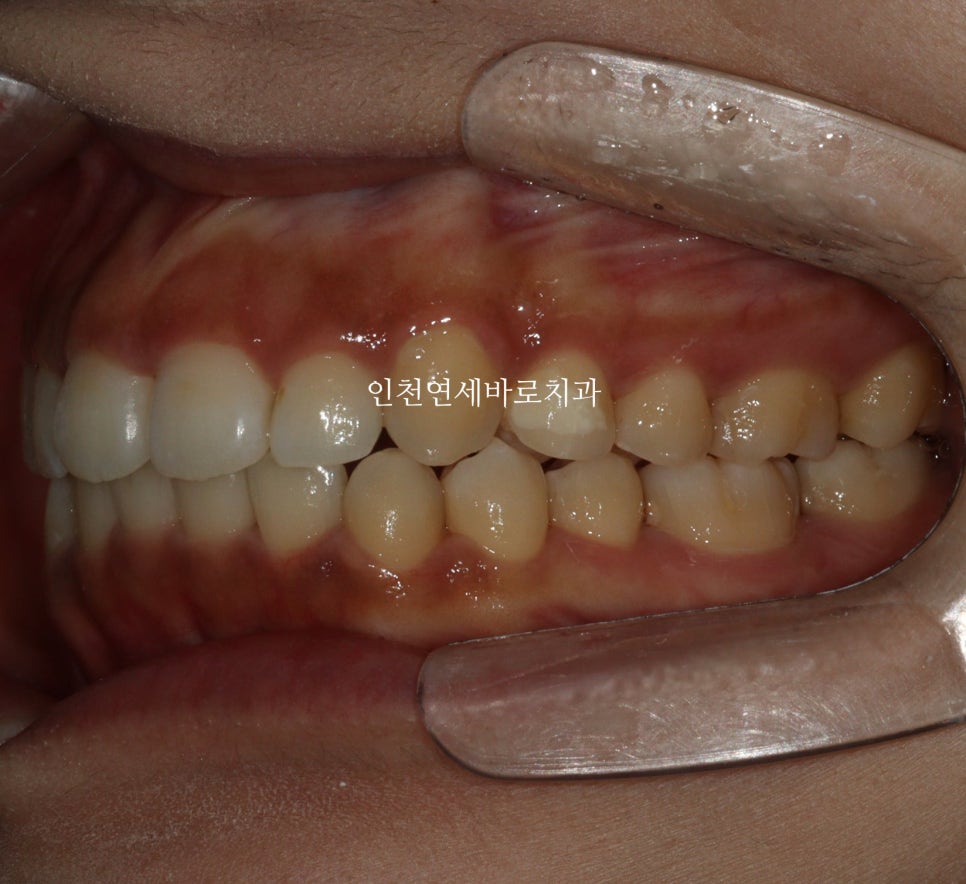

2024년 6-7월 – 치료 중간 단계

시작 후 약 4-5달 후 사진입니다.

인비절라인은 투명교정장치만 착용하는 경우가 대부분이긴합니다.

하지만 이 환자분 처럼 고무줄을 동반해야하는 경우도 있습니다.

치료 전 원장님과의 상담을 통해 정확한 치료계획을 듣고 시작하시는 것이 좋습니다